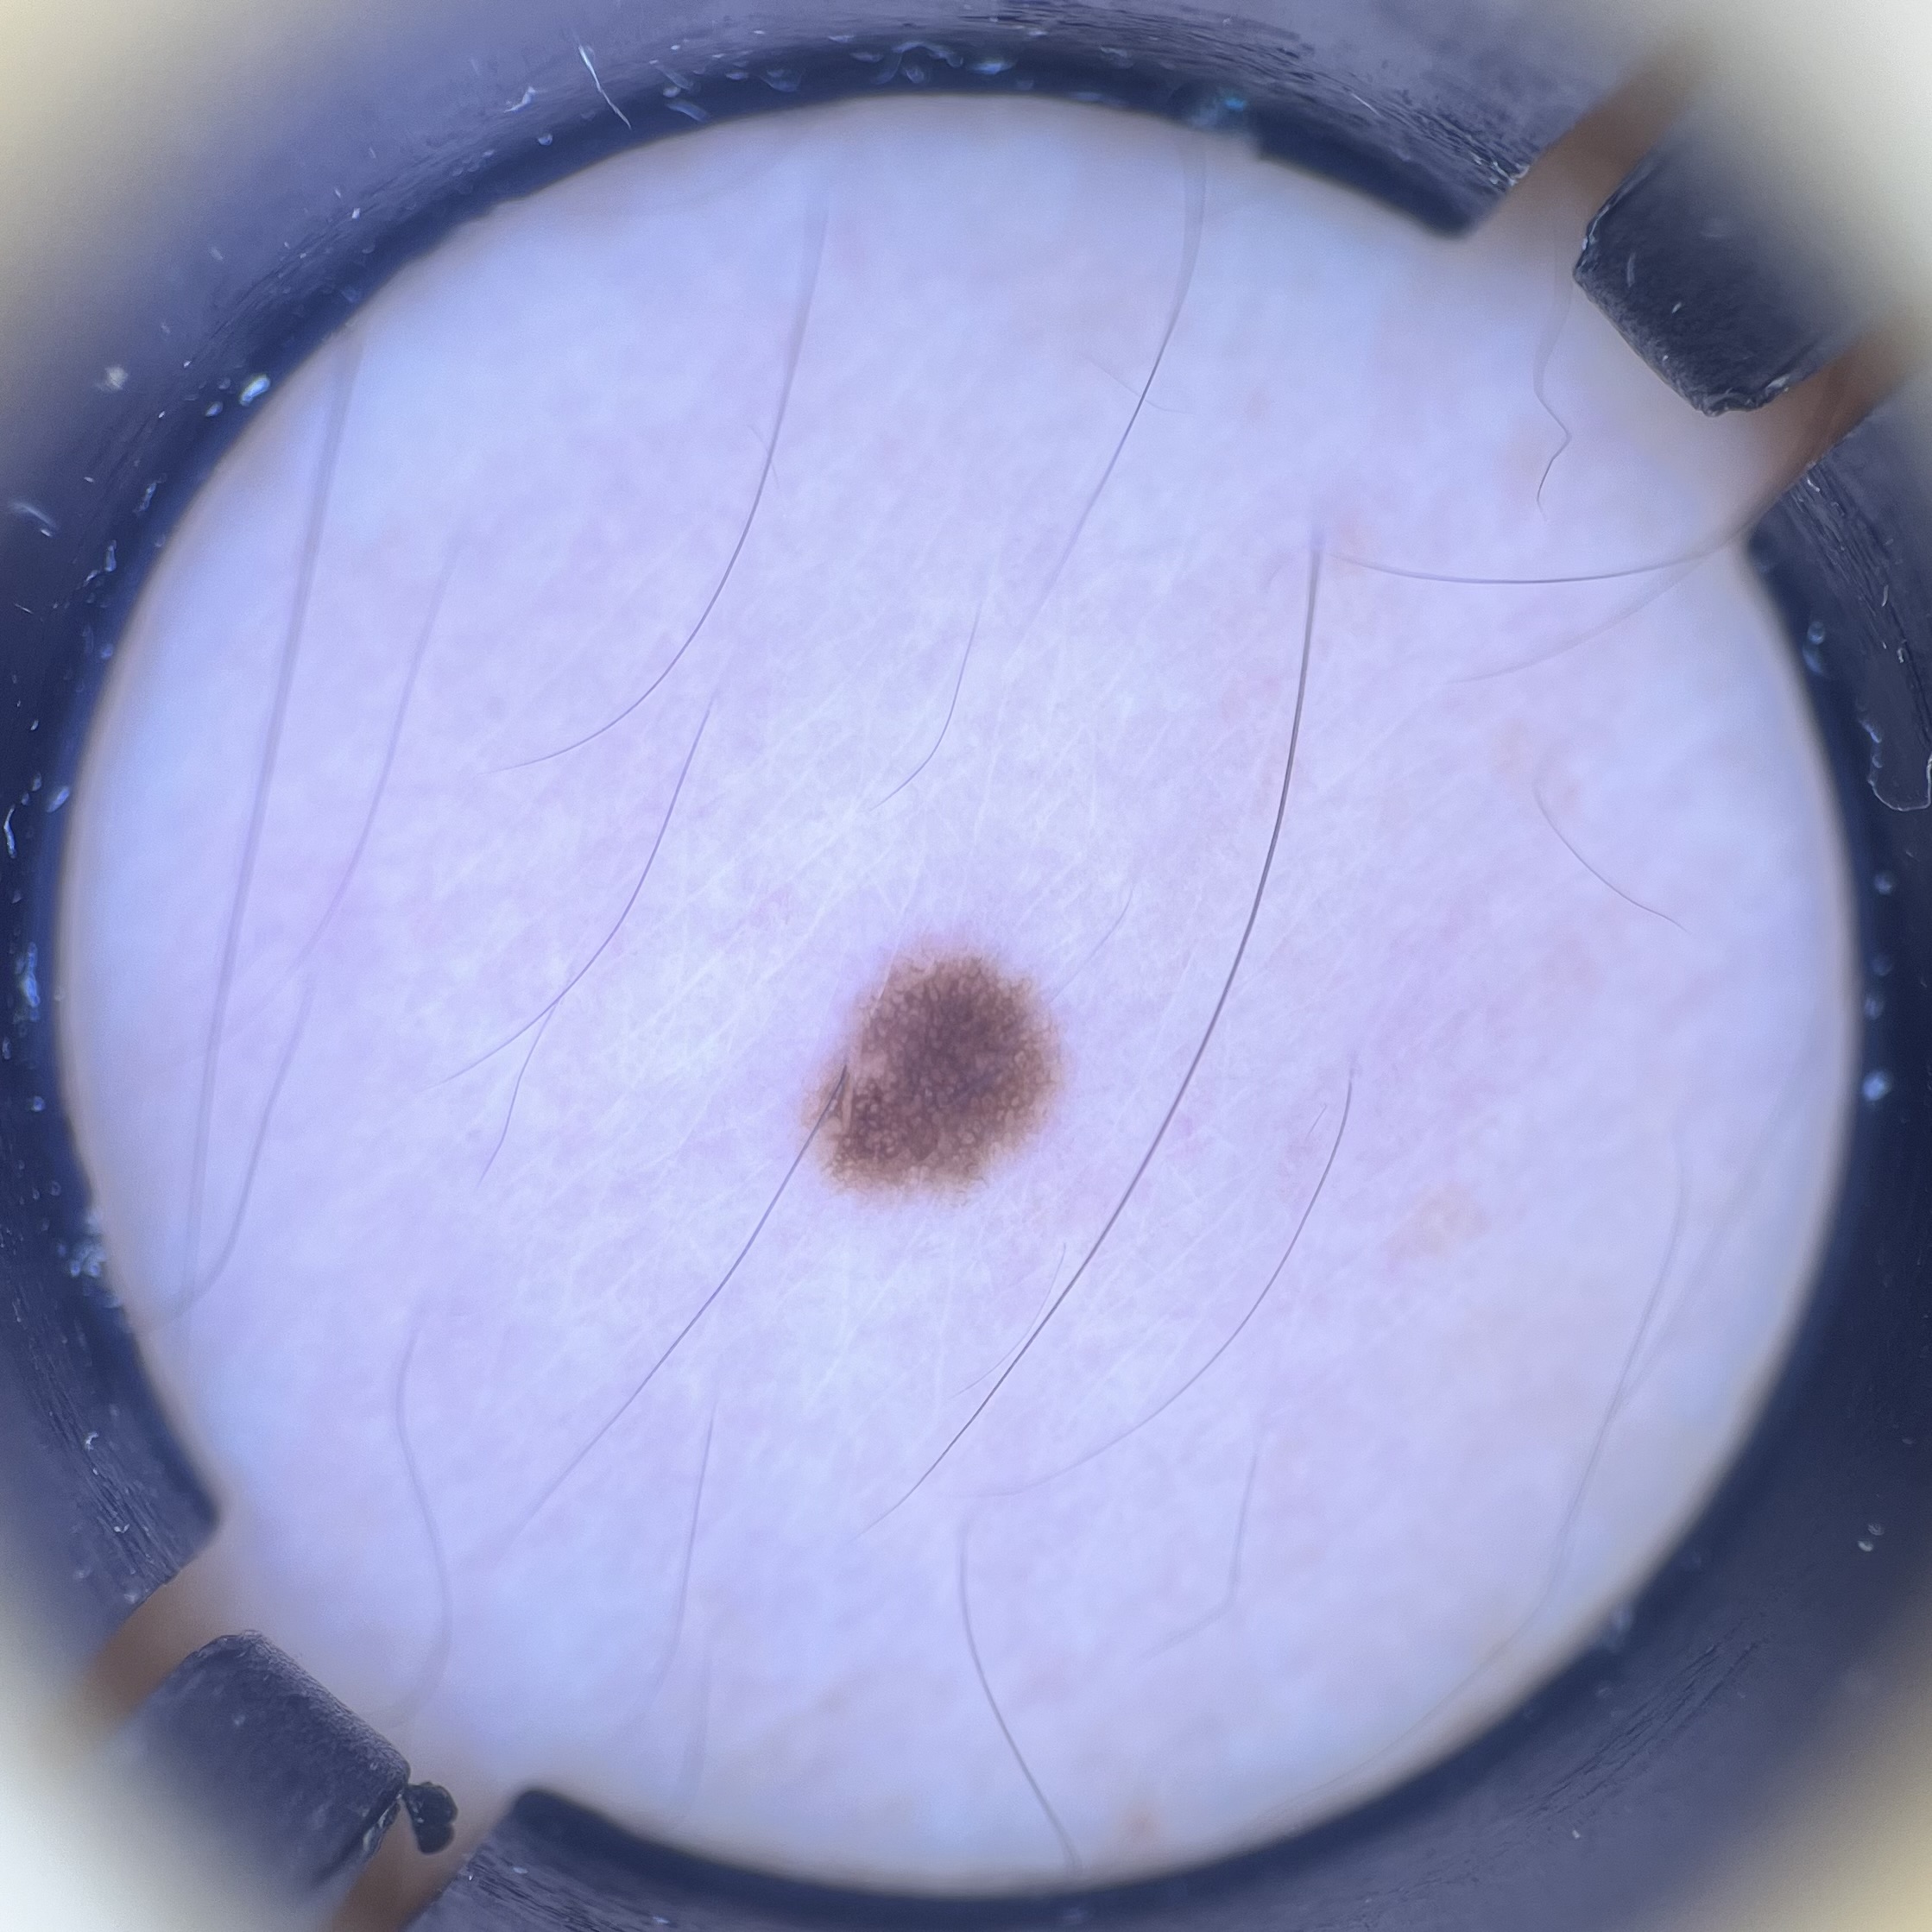

また、当院では皮膚科医が在籍していますので、ダーモスコピー検査を行うことも可能です。

京都駅前美容外科では、大きさ、深さ、場所などのホクロやイボ、血管腫の状態やご希望に合わせて、高周波焼灼法、手術、くり抜き法から最適な治療法をご提案いたします。

首イボや血管腫、小さいホクロだけではなく、レーザー治療では取れないような盛り上がりのあるホクロにも対応しています。